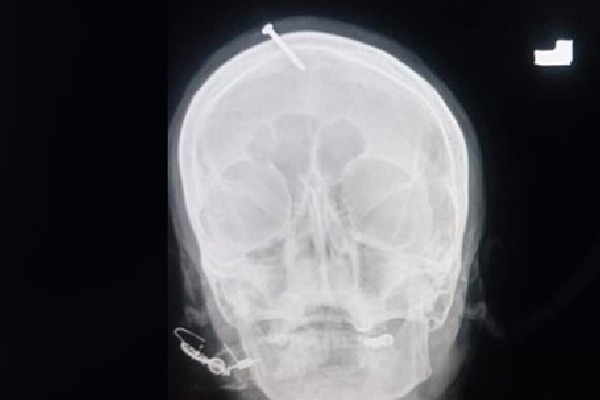

గర్భిణి తలలో మేకు ఉన్న ఎక్స్రే ఫొటోలు అక్కడి సోషల్ మీడియాలో చక్కర్లు కొడుతున్నాయి. ఈ ఘటనపై ఫిర్యాదు అందనప్పటికీ పోలీసులు రంగంలోకి దిగారు. ఆసుపత్రికి వెళ్లి దర్యాప్తు చేపట్టారు. విషయం వెలుగులోకి రావడంతో నకిలీ బాబా పరారయ్యాడు. ఇప్పుడతడి కోసం పోలీసులు గాలిస్తున్నారు.